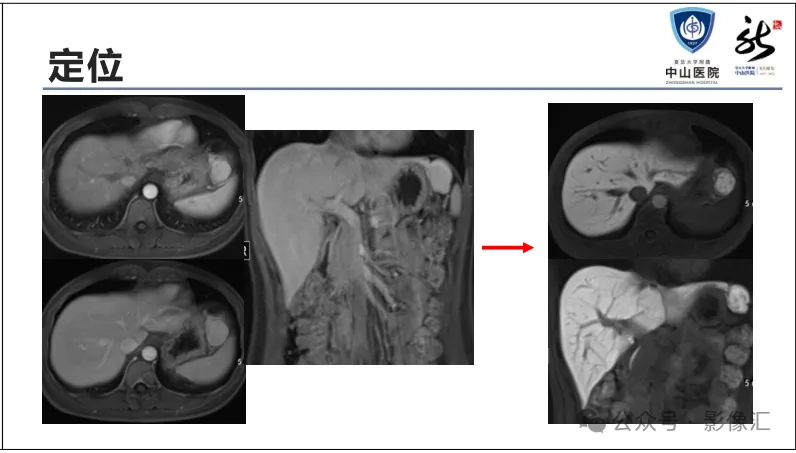

>【精品课件】如何正确判读肝胆特异性对比剂增强图像?

肝胆特异性对比剂增强肝胆图像判读方法与策略,课件来源于网络,作者复旦大学附属中山医院放射科饶圣祥教授。